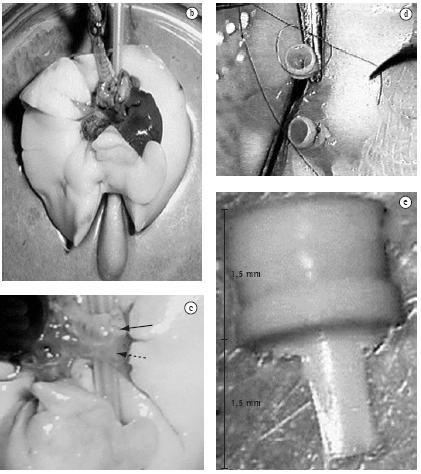

Foram utilizados ratos da raça Wistar pesando entre 300-400 g. Todos os animais foram tratados conforme o Ethical Code for Animal Experimentation da Organização Mundial da Saúde.(14) Cada animal doador era anestesiado em câmara com halotano, seguido por administração de ketamina (50 mg/kg) e xilazina (15 mg/kg), por via intraperitoneal. O animal era traqueostomizado com um cateter de venopunção tipo Abocath® #14 (Abbott Laboratories, Abbott Park, IL, EUA) e submetido a ventilação controlada a volume: capacidade vital, 10 mL/kg; freqüência respiratória, 65 rpm; e pressão expiratória final positiva, 2 cmH2O. Posteriormente, procedia-se uma toracotomia bilateral longitudinal através das linhas hemiclaviculares, com secção transversa ao nível do apêndice xifóide. Após a administração endovenosa de heparina (100 UI/100 g), seccionava-se a veia cava inferior, a aorta torácica e as aurículas direita e esquerda para a perfusão da solução de preservação. Procedia-se com a secção e canulação da artéria pulmonar com um cateter de venopunção #16 (Figura 1a) e iniciava-se a perfusão pulmonar com 20 mL de solução de preservação (Perfadex®; Vitrolife, Göteborg, Suécia) com uma pressão de 30 cmH2O, a 4 °C. Durante todo o procedimento o pulmão era ventilado com oxigênio a 100%. Terminada a perfusão, e com os pulmões semi-insuflados, ligava-se a traquéia e procedia-se a extração do bloco cardio-pulmonar. A seguir, eram isolados os elementos do hilo pulmonar esquerdo (Figuras 1b e 1c) e inseridos os cuffs (confeccionados a partir de cateteres de venopunção #14 ou #16 com 3 mm de extensão, que apresentam uma lingüeta na sua base com 1,5 mm) (Figura 1e). O cuff #16 era sustentado pela sua lingüeta e com o auxílio de duas pinças microcirúrgicas a artéria pulmonar passava através do cuff, e invertia-se o endotélio desta ao redor da circunferência do cuff, sendo esta fixada por um fio monofilamentar 7-0 ou 8-0 (Figura 1d). O mesmo procedimento era realizado para o brônquio e veias pulmonares utilizando cuffs #14. Após o preparo do pulmão para transplante, este era armazenado a temperaturas entre 4 °C e 8 °C por períodos variáveis de tempo, dependendo do objetivo de cada experimento.

O animal receptor era sedado, anestesiado e intubado via orotraqueal. Posteriormente, eram selecionados os parâmetros ventilatórios previamente descritos para o doador e canulada a artéria carótida direita ou esquerda, com um Abocath® #24 para monitorização hemodinâmica. O animal, em decúbito lateral direito, era submetido a uma toracotomia póstero-lateral esquerda no 5º espaço intercostal. Após liberado o ligamento pulmonar, o pulmão esquerdo era exteriorizado e mantido fora da cavidade torácica por um clipe metálico (Figura 2a). Depois de isoladas as estruturas hilares (artéria, brônquio e veia), estas eram clampeadas com um clampe hemostático. Estas estruturas eram envolvidas com um fio de sutura de 7-0 ou 8-0 pronto para ser amarrado assim que cada estrutura fosse canulada. O implante iniciava-se através da secção da parede lateral da artéria na sua porção ventral, progredindo-se cuidadosa e lentamente o cuff da artéria do doador para dentro da artéria receptora e a fixação desta com aquele fio de sutura colocado previamente ao redor da artéria (Figura 2b). Este mesmo procedimento era realizado para o brônquio e a veia, respectivamente e nesta ordem. Uma vez implantado o pulmão, procedia-se com a abertura do clampe brônquico, seguido da veia e artéria respectivamente (Figura 2c), com posterior retirada do pulmão esquerdo do receptor. Após o término do transplante, era realizado o clampeamento do pulmão contralateral. Esta variante do modelo original permite a avaliação exclusiva do pulmão transplantado (Figura 2d). Este procedimento é realizado pela mesma incisão da toracotomia, retraindo-se o pulmão transplantado em projeção anterior com o auxílio de um cotonete, disseca-se a face mediastinal posterior, permitindo a identificação do hilo pulmonar direito e facilitando o seu clampeamento. A oclusão do hilo pulmonar direito pode ser realizada em bloco ou efetuada apenas a ligadura da artéria pulmonar direita. Esta variação depende exclusivamente do objetivo do estudo a ser realizado. Quando realizada a oclusão total do hilo pulmonar, deve-se reduzir o volume de ar corrente para 5 mL/kg, para evitar a hiperinsuflação do pulmão transplantado e conseqüente lesão induzida pelo ventilador. Na eventualidade de ligadura da artéria pulmonar contralateral apenas, o volume corrente permanece o mesmo. Também podem ser realizados clampeamentos temporários da artéria pulmonar direita com o objetivo de coletar gasometrias arteriais que representem apenas a troca gasosa do pulmão transplantado. Após realizado o transplante e o clampeamento hilar contralateral, o pulmão é insuflado e a parede torácica fechada por planos. Terminado o período de observação, é realizada a extração do bloco cardiopulmonar sendo este fixado em paraformaldeído a 4% ou armazenado a -70 °C.